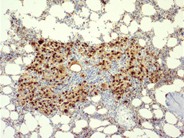

Bone marrow granuloma - 2.

Category: Reactive Marrow

The granulomatous lesion is shown at higher magnification to illustrate the cellular composition of macrophages with eosinophilic cytoplasm and scattered lymphocytes and plasma cells.